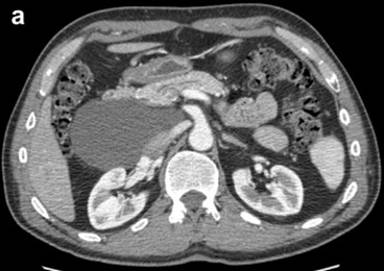

A 60-year-old asymptomatic male was found to have an abdominal cystic lesion incidentally on computed tomography (CT) scan of the coronary vessels during routine cardiology work up in preparation for an ablation of atrial fibrillation. (Figure 1a). The patient subsequently underwent transabdominal ultrasound which showed a multiloculated anechoic cystic mass adjacent to the body and head of the pancreas. No evidence of pancreatic or biliary duct dilation was seen. The patient has no history of heavy alcohol use (Figure 1b). There was no personal or family history of pancreatic or hepatobiliary disease. Physical examination was unremarkable including no evidence of abdominal tenderness or masses. Routine laboratory tests at the time were all normal including: serum electrolytes, complete blood count, and biochemical tests of hepatic and renal function.

Figure 1. a. Contrast enhanced abdominal CT scan showing a cystic lesion adjacent to the head of the pancreas and anterior to the right kidney from Case #1. b. Linear EUS image showing the anechoic cyst with several thin septae from the same patient. |